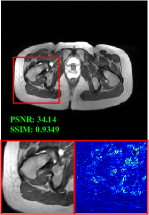

Figure 5 provides the qualitative comparison of the various methods on the four datasets at a scale of 4. The top, second, third, and bottom rows are the SR results under the FastMRI, clinical brain, clinical tumor and clinical pelvic datasets, respectively. The red boxes indicate the zoom-in region of complicated anatomical structures along with their corresponding error maps. Note that the brighter textures in the error maps, the lower the quality of the reconstructed images. As can be seen, compared to methods based on Transformers and CNNs, diffusion-based methods like DisC-Diff and DiffMSR (Ours) are capable of reconstructing high-realistic images with promising reconstruction metric scores (PSNR and SSIM). Nevertheless, while DisC-Diff can reconstruct high-precision MR images, it does not preserve the structure present in the original HR images, introducing some additional information that can affect medical diagnosis. In contrast, our method combines DM and PLWformer, which can preserve the original image’s structure while restoring high-frequency information.

In this section, we present more visual qualitative comparisons. Figures 8, 9, 10, and 11 show the reconstruction results of each method in FastMRI, clinical brain, clinical tumor, and clinical pelvic, respectively. As can be seen, although DisC-Diff can reconstruct MR images with high-frequency information, it fails to preserve the structure and content of the original Target HR image effectively, resulting in image distortion. In contrast, our proposed DiffMSR can restore high-frequency information while preserving the structure of the original HR image, indicating the effectiveness of the joint use of DM and PLWformer.